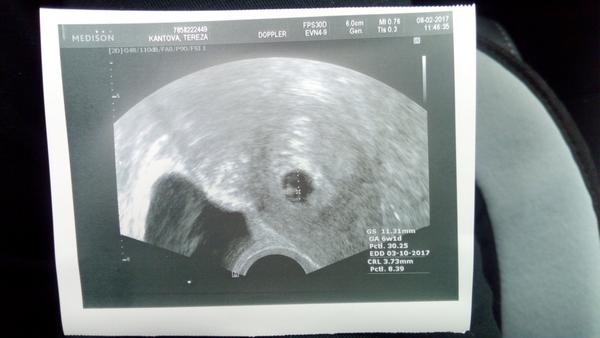

@terka228 délka je crl. A gratulujiiiii!

@terka228 jinak dle měření, gestacni stáří, je zapsáno 6+1, to odpovídá, ne? A jinak počítám, že ten první rozměr...cca 11 mm bude ta zmerena velikost celého vacku. Ostatní zkratky neznám...